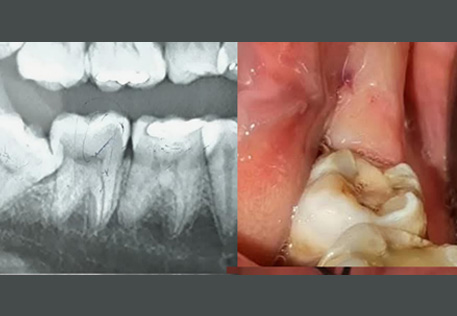

Comprehensive oral examination with digital X-rays to assess the position and condition of your wisdom teeth.

Before / After